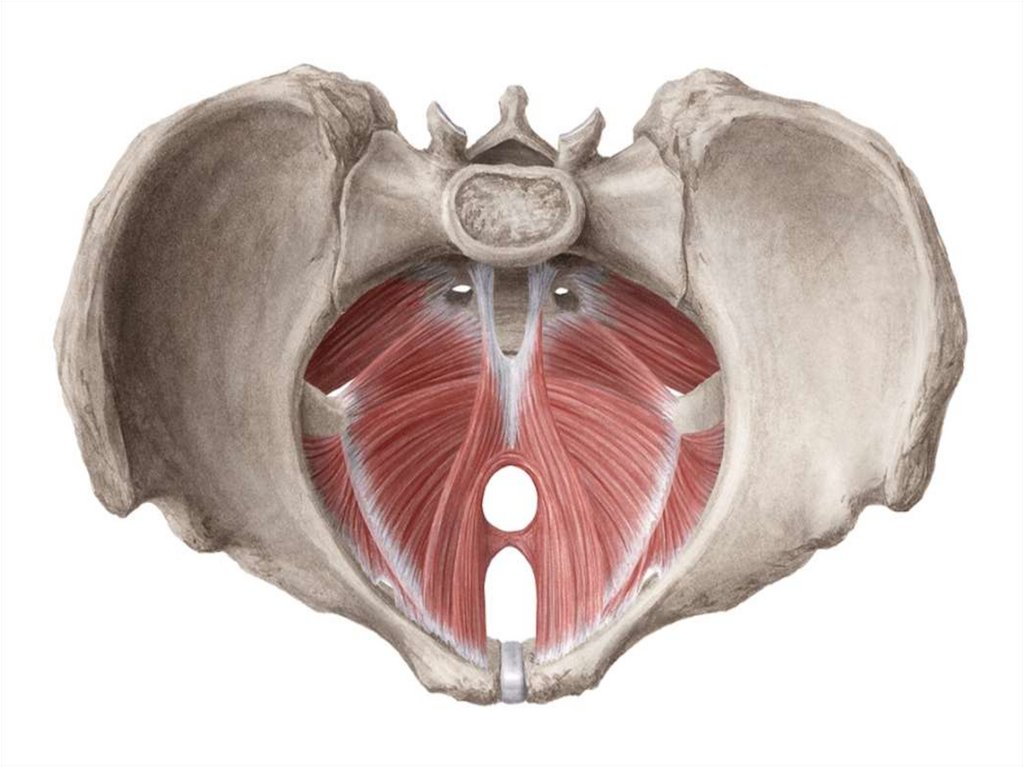

11. Фиксирующие связки представлены такими элементами:

• Поперечная связка матки. Ее также называют

главной. Окружает шейку матки на уровне

внутреннего зева. Вплетается в тазовую фасцию и

фиксирует матку в определенном положении к

тазовому дну.

• Пузырно-маточные и лобково-пузырные связки.

Протянуты от матки к мочевому пузырю и лобку.

• Крестцово-маточные связки. Начинаются от задней

поверхности матки чуть ниже ее внутреннего зева,

охватывают с двух сторон прямую кишку и

вливаются в тазовую фасцию на уровне крестца.